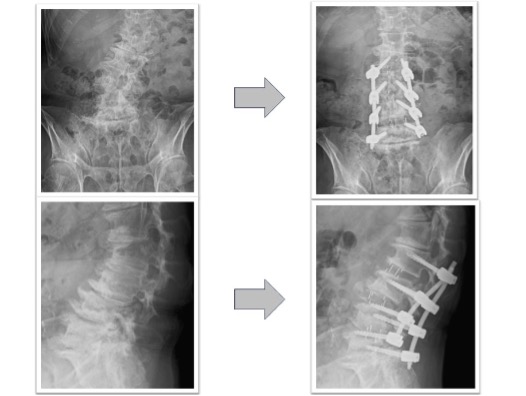

腰椎固定術実例(OLIF症例、*患者様の許可を得て掲載しています)

椎間板ヘルニア(図1)

体動困難を伴う激烈な下肢痛に対してL4/5の固定術を実施。術前に認められていたL4/5の椎間板ヘルニアがOLIFによる固定術後、間接除圧効果などによって消失しています(図1、赤丸)。レントゲンでは椎間ケージと腰椎L4とL5を固定する椎弓根スクリューが確認できます(図1、下段)。本症例の傷は左わき腹に4-5cmと、背部のスクリュー刺入部位に2㎝弱の傷が4つとなります。術後、痛みは消失しました。

図1

腰椎すべり症+椎間板ヘルニア(図2)

下肢痛で来院し歩行困難のため手術となりました。術前認められていたL3/4の椎間板ヘルニアがOLIFによる固定術後消失(赤丸)、またL4/5に認められていた変性すべり症による椎体のずれ、不安定性も術後は元の脊椎の並びに矯正された状態で固定されています(黄丸)。術後は症状消失し、元通り歩行可能となりました。

図2

変性側弯を伴う多椎間の椎間板ヘルニア、脊柱管狭窄症(図3,4)

下肢痛、歩行障害、腰痛で来院、手術となりました。術前後のレントゲンで3椎間のOLIFによって術後側弯症が改善され、脊椎の並び(アライメント)が矯正されています(図3)。また、術前後のMRIでは施術した部位の椎間板ヘルニアおよび脊柱管狭窄がOLIFの間接除圧効果によって改善し、神経への圧迫が解除されています(図4)。術後は歩行可能、下肢痛腰痛も改善、また結果として数センチ身長が回復しています。

図3

図4